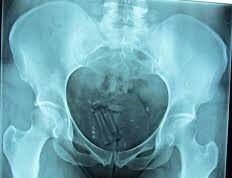

Jujuy: un preso que ocultaba un paquete en su recto terminó hospitalizado

Este fin de semana, un interno del Servicio Penitenciario jujeño, fue trasladado de urgencias al Hospital. Quedó hospitalizado debido a que ocultó en su...